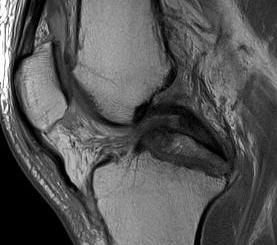

MRI

Advantage

- defines level of conus

- may need anterior rather than posterior surgery if lesion above conus